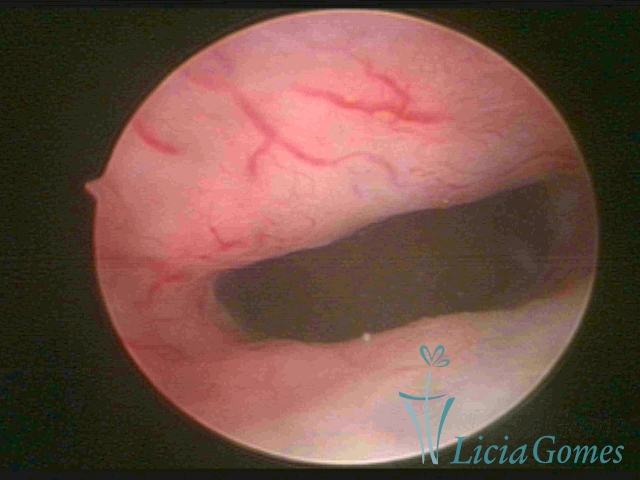

Retração da cicatriz de cesárea, reentrância com posterior abaulamento em região ístmica